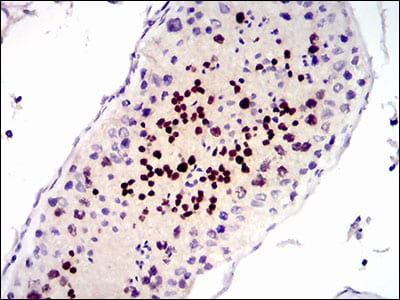

- Immunohistochemical analysis of paraffin-embedded human testis tissues using CDK4 mouse mAb with DAB staining.